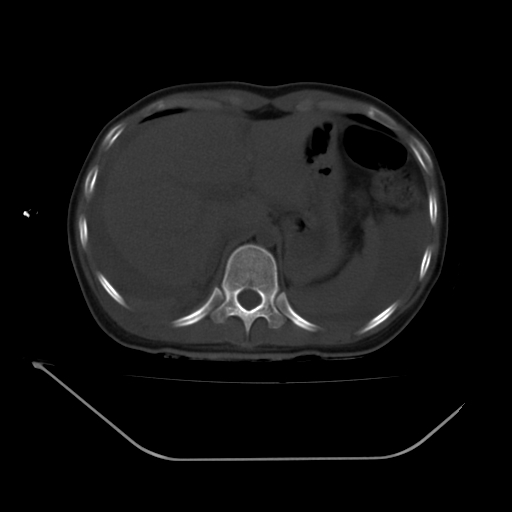

以下是引用liuyue在2008-7-19 13:02:00的发言:[br]1.肝右叶后下段及右肾挫裂伤伴腹腔积血。[br]2.右侧多发性肋骨骨折、横突骨折、右髂骨骨折伴周围软组织挫伤。[br]3.右侧腰大肌肿胀,并可见低密度影,如为气体,则肠道挫裂伤待除外。

以下是引用zhengfaming在2008-7-19 14:42:00的发言:[br]1.肝右叶后下段及右肾挫裂伤伴腹腔积血。脾脏挫裂伤待排[br]2.右侧多发性肋骨骨折、横突骨折、右髂骨骨折伴周围软组织挫伤。[br]3.右侧腰大肌肿胀,并可见低密度影,如为气体,则肠道挫裂伤待除外

以下是引用道哥在2008-7-19 16:52:00的发言:[br]肝右叶后下段及右肾挫裂伤、脾破裂伴腹腔积血。[br]2.双侧多发性肋骨骨折、横突骨折、右髂骨骨折伴周围软组织挫伤。[br]3.右侧腰大肌肿胀,并可见低密度影,如为气体,则肠道挫裂伤待除外。